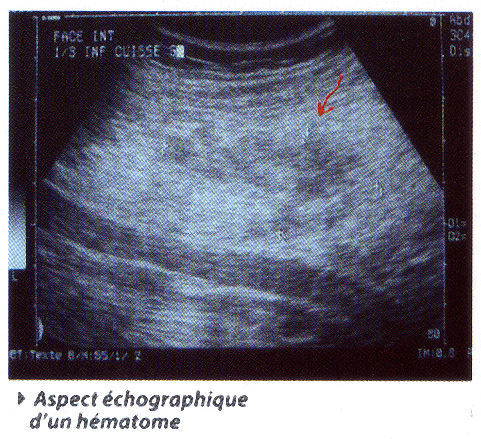

L'article du Dr Mustapha BOUSSOUGA, développe également les aspects physiologiques, les causes et les conséquences, les principaux signes cliniques et les examens complémentaires nécessaires, notamment les dosages biologiques et l'imagerie radiologique, notamment, la radiologie standard, l’échographie, l'IRM et la scintigraphie ainsi que tous les traitements adaptés.